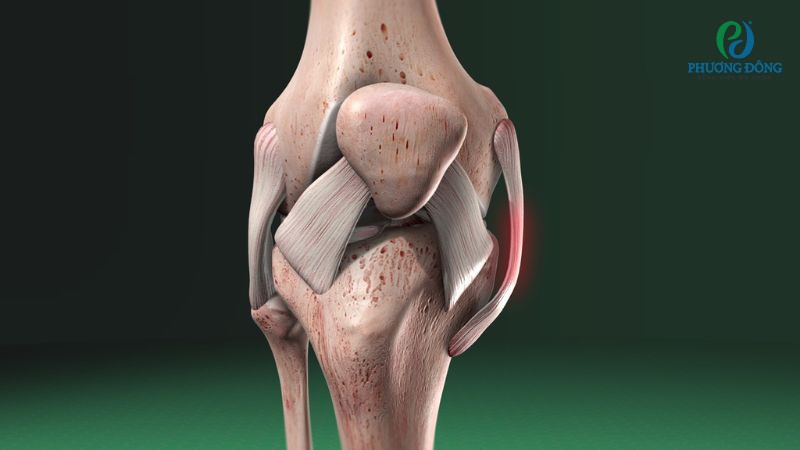

1. Chấn thương dây chằng bên trong gối (MCL) là gì?

Chấn thương dây chằng bên trong gối (MCL) là tình trạng tổn thương dây chằng bên trong, một trong những dây chằng chính của khớp gối. Tổn thương xảy ra có thể làm rách một phần hoặc đứt hoàn toàn dây chằng, làm mất cấu trúc giải phẫu vốn có.

Hình ảnh chấn thương dây chằng bên trong gối (MCL)

Dây chằng giữa gối có cấu trúc dẹt, rộng, trải dài từ đầu trên xương cẳng chân đến mặt trong đầu dưới xương đùi. Loại dây chằng này có nhiệm vụ duy trì sự ổn định cơ học của khớp gối, kiểm soát các cử động quá mức và giới hạn phạm vi di chuyển của khớp gối.